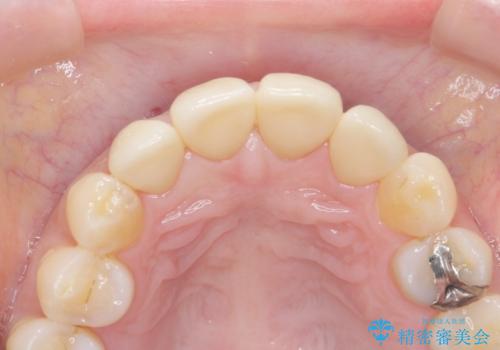

- フルジルコニアクラウン・仮歯 9.9万円×4費用は治療当時の料金となります

適合の良い被せ物が入りました。

樹脂の素材とは違い、セラミックやジルコニアの素材の被せ物は劣化をしません。また、虫歯の再発リスクも低くなります。

形、色、共に満足して頂けました。